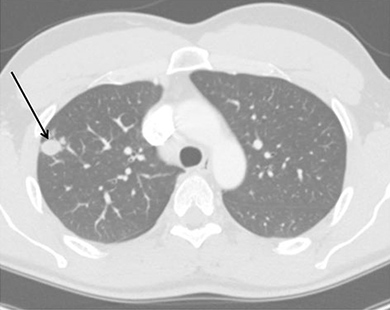

Residual nodule following resolution of primary infection.

Approximately 5% of patients with resolution of primary pneumonic infiltrate can develop a pulmonary nodule or cavity. The initial identification of a coccidioidal infection could be a pulmonary nodule or cavity found incidentally on imaging studies. Nodules due to Coccidioides are often difficult to differentiate from malignancy, especially in persons who have not been diagnosed with coccidioidomycosis previously. Positron emission tomography (PET/CT) has been employed, but it is not always able to differentiate malignancy from coccidioidal pulmonary nodules. In an endemic region of California with a lung nodule program, approximately one-third of nodules are attributable to Coccidioides. Certain factors may have increased association with a coccidioidal nodule rather than malignancy, including male sex, age <55, lack of underlying pulmonary disease, farm labor or construction occupations, a nodule < 2 cm in size, and a nodule described as diffuse or smooth in appearance (1). Immunologic assays may be less reliable in this setting, and often a bronchoscopy or biopsy is required to establish the diagnosis via histopathology, culture, and possibly PCR. Asymptomatic nodules attributed to coccidioidomycosis do not require treatment. When such lesions are stable over time with repeated radiographic imaging over 2 years in combination with a benign clinical course, no intervention is necessary. Any treatment decision should take into account patient risk factors, serologic studies, and characteristics of the lesion.